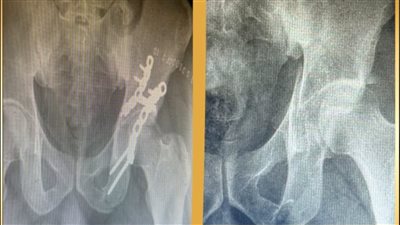

إنجازان طبيان في مجمع الأقصر الطبي.. تشخيص دقيق وجراحات عظام متقدمة تعيد الحركة للمرضى

جراحات العظام